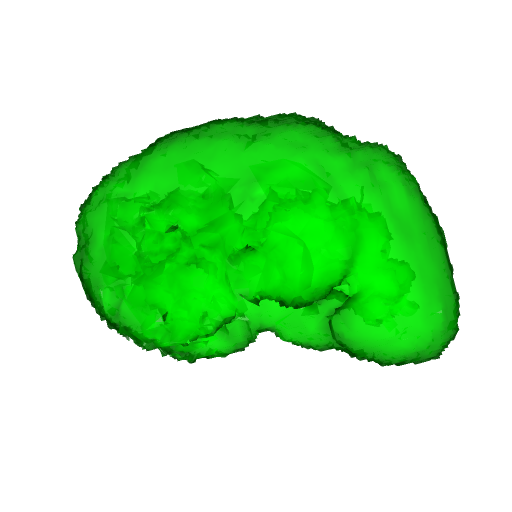

For MSER tracking, Donoser and Bischof [5] presented three different applications; license plate tracking, face tracking and the segmentation of a fiber network. In the third application, a fiber network is reconstructed in 3D by tracking a slice of the data along the axis orthogonal to the image data. Analogously, we track organs in slices of a Computed Tomography (CT) scan, to generate a 3D segmentation. We use the CT data provided in the 3DIRCADb dataset222The dataset is available on http://ircad.fr/research/3d-ircadb-01 [14].

To initialize the tracking process, the organ is segmented in an arbitrary slice of the CT data by a bounding box. The most stable MSHR is then selected in the initialization process for tracking. The respective MSHR is tracked through the slice data along the axis orthogonal to the image data. An example of the tracked regions is visualized for two examples in Fig. 7. Given the segmentations of the single slices, the organ can be reconstructed in 3D. We compare the reconstruction for MSER and MSHR tracking in Fig. 8. To enhance the visualization, the datapoints are triangulated and the surface normals calculated. Since the contrast of the organs can be very low in CT images, the MSER tracking has difficulties catching the organ boundaries. Furthermore, the organ is sometimes partely lighter and darker than the background, which may lead to MSER tracking failure. The proposed MSHR tracking copes well with these difficulties, and the reconstructions are significantly better.

Figure 7: Two examples sequences from the 3DIRCADb dataset [14]. Given an initial selection of a single slice (the middle image in (a) and (b)) of the organ, the proposed MSHR tracking tracks the region forward and backwards in space. The segmented slices can be used to reconstruct the organ, see Fig. 8 for an example reconstruction.